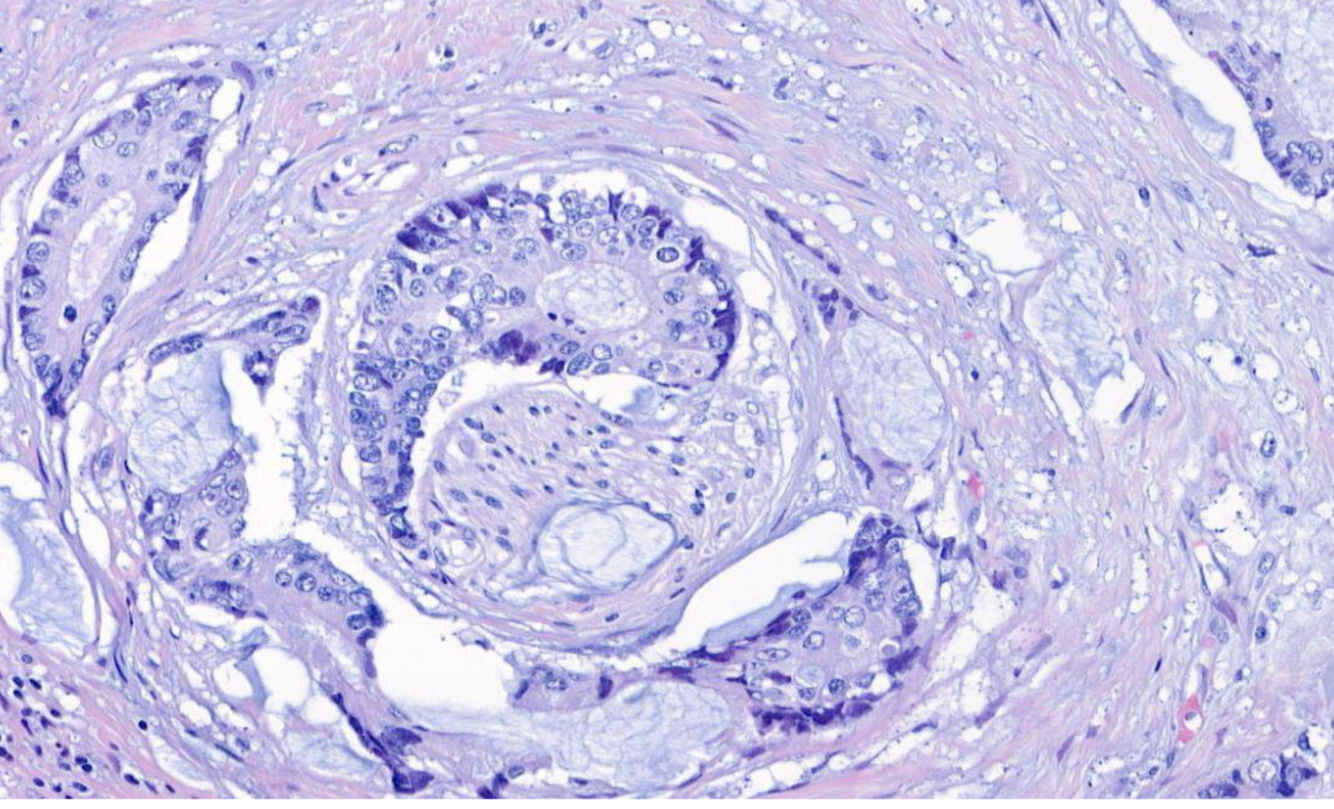

Diagnose?

Pleomorphes Speicheldrüsenadenom = BENIGNE

80% in der Parotis -> nicht destruktiv, nicht invasiv, nur verdrängend

v.a .Parotis, benigne, aufgebaut aus bindegewebiger Kapsel und epithelialen und mesenchymalen Gewebe (v.a. Knorpelgewebe)